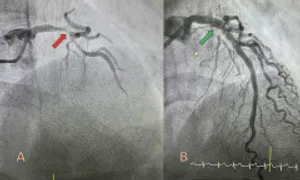

Thiếu máu cơ tim do hẹp mạch vành

16/09/2024

Xem chi tiết